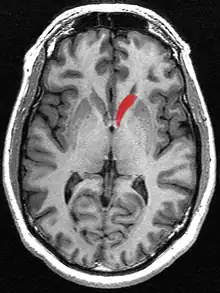

![]() Caudate nucleus (in red) shown within the brain | |

The caudate nuclei are near the center of the brain, sitting astride the thalamus. There is a caudate nucleus in each hemisphere of the brain. Each nucleus is C-shaped, with a wider "head" (caput in Latin) at the front, tapering to a "body" (corpus) and a "tail" (cauda). Sometimes a part of the caudate nucleus is called the "knee" (genu).[7] The caudate head receives its blood supply from the lenticulostriate artery; the tail of the caudate receives its blood supply from the anterior choroidal artery.[8]